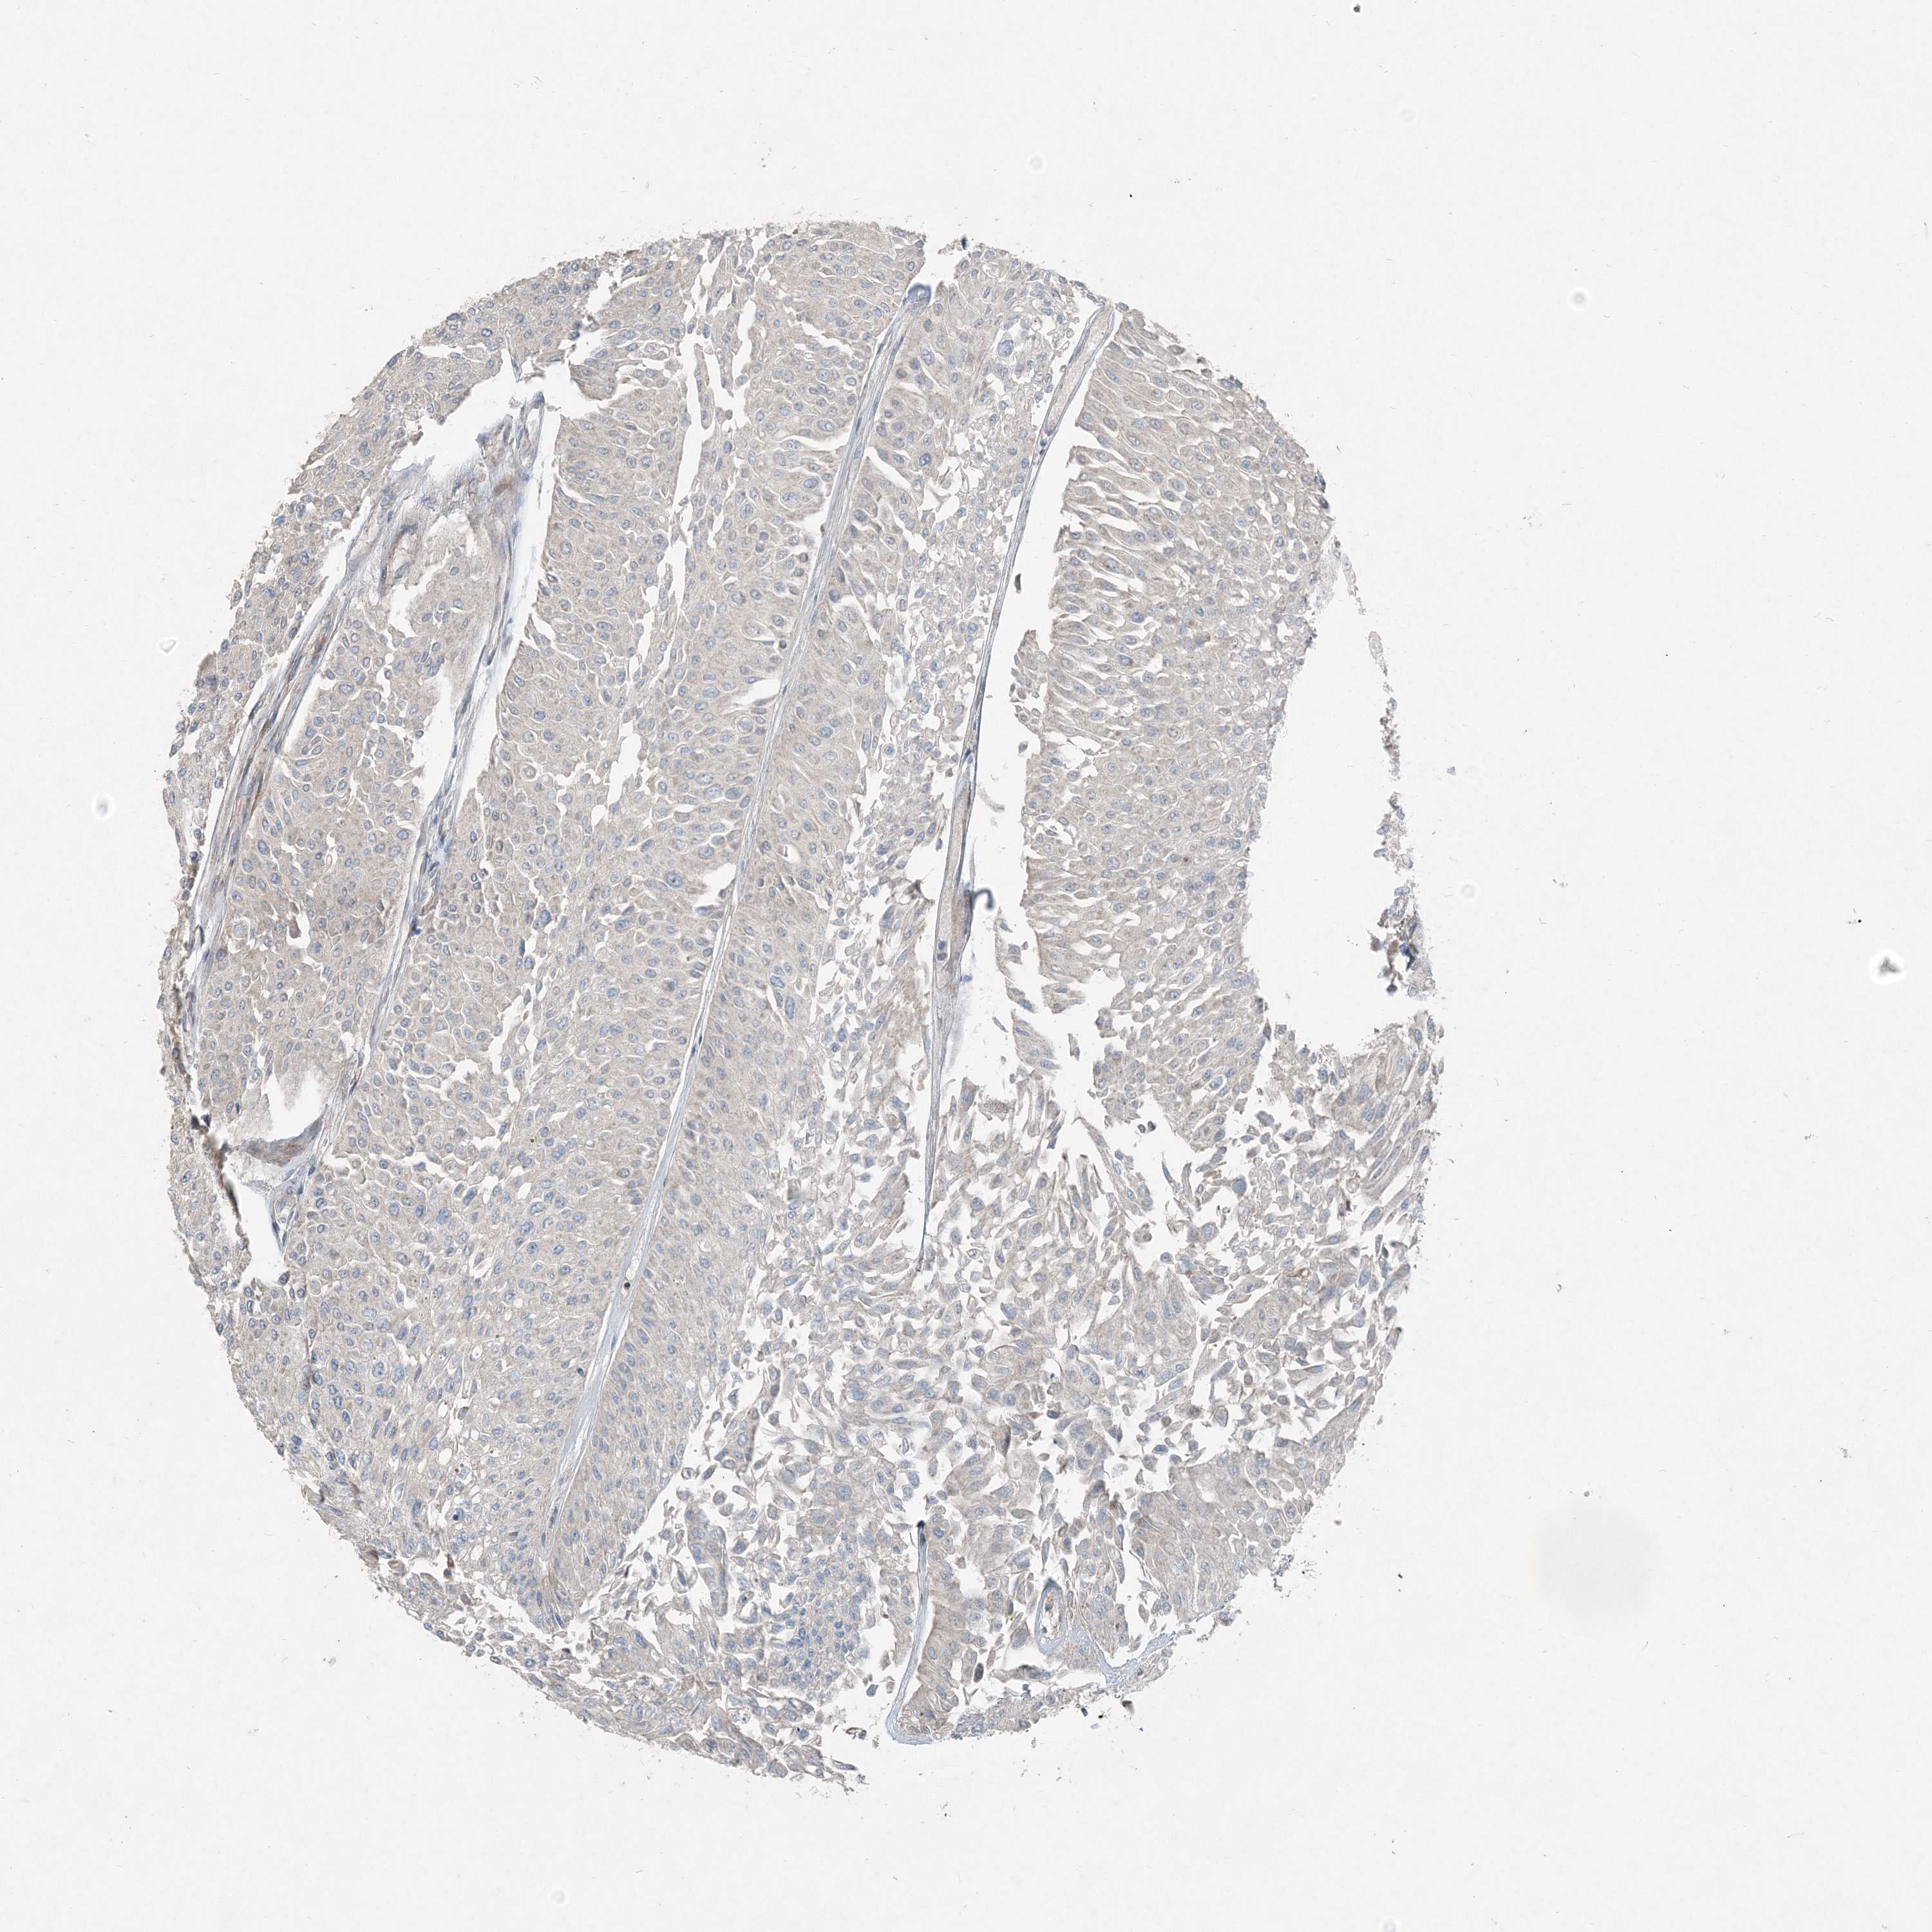

UROTHELIAL CANCER - Protein expressioni

A mouse-over function shows sample information and annotation data. Click on an image to view it in a full screen mode. Samples can be filtered based on level of antibody staining by selecting one or several of the following categories: high, medium, low and not detected. The assay and annotation is described here.

Antibody stainingi

Antibody staining in the annotated cell types in the current human tissue is reported as not detected, low, medium, or high, based on conventional immunohistochemistry profiling in selected tissues. This score is based on the combination of the staining intensity and fraction of stained cells.

Each image is clickable and will lead to virtual microscopy that enables deeper exploration of all samples and also displays staining intensity scores, fraction scores and subcellular localization as well as patient and tissue information for each sample.

Antibody HPA036714

Antibody HPA036715

Staining

High

Medium

Low

Not detected

Intensity

Strong

Moderate

Weak

Negative

Quantity

>75%

75%-25%

<25%

None

Location

Nuclear

Cytoplasmic/membranous

Cytoplasmic/membranous,nuclear

Urothelial carcinoma, Low grade